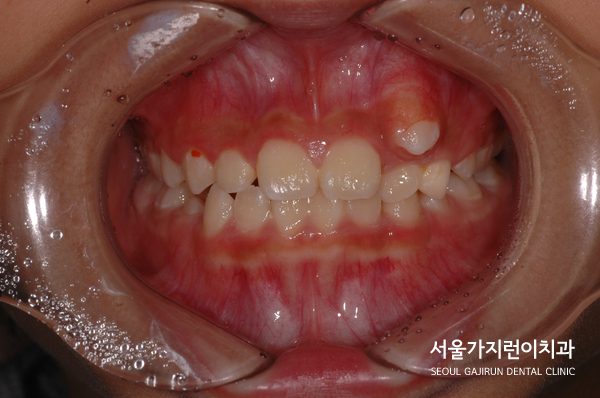

아직 성장 중이라는 부분을 활용해 치아교정을 이용한 케이스에 혹시 모를 상황을 대비했는데요. 상악골이 조금 더 나와보이는 이유는 아이가 하악골 과성장 패턴을 보였기 때문에 잔여 성장으로 자랄 것을 예상하여 맞춘 케이스입니다. 만약 이때 딱 맞춰 교정할게 된다면 앞니의 맞물림이 절단교합 혹은 교차교합으로 될 가능성이 높았기 때문에 이를 방지하기 위해 과수정되게 끝낸 것이죠.

심한 송곳니 덧니의 비발치 성장기 교정 케이스